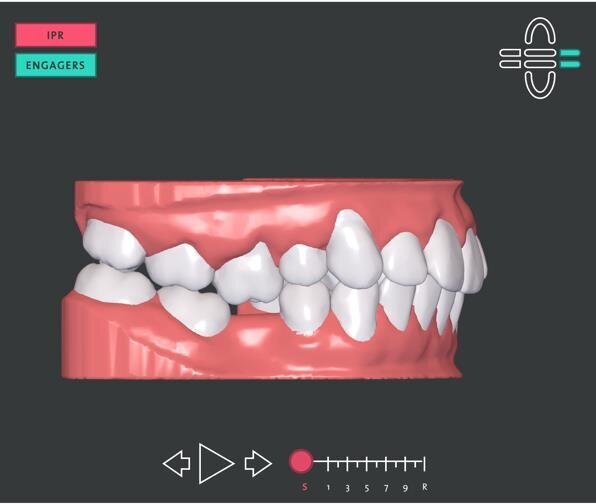

Figg. 4a, 4b - Pianificazione dei momenti. Si noti l’intrusione dell’elemento 1.6.

La simulazione del setup iniziale inviato da ClearCorrect® ha previsto un trattamento con 10 allineatori per arcata da sostituire ogni 14 giorni per un totale di quasi 20 settimane, poco meno di 5 mesi di terapia (Figg. 4a, 4b). La quantità totale di riduzione interprossimale richiesta è stata pari a 1.8 mm localizzata nell’emiarcata superiore destra e suddivisa nelle zone interprossimali tra il primo molare e il premolare, tra il premolare e il canino, tra il canino e l’incisivo laterale ed infine tra l’incisivo laterale e l’incisivo centrale. Sono stati, inoltre, posizionati 3 engagers su tre elementi dell’arcata superiore: canino e incisivo laterale di destra e incisivo laterale di sinistra per favorire i movimenti di modifica di tip e torque degli elementi anteriori superiori (Fig. 5).